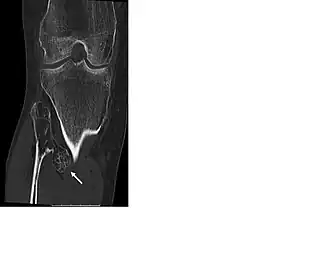

HME wordt vaak vastgesteld aan de hand van röntgenfoto's. In het algemeen wordt aangenomen dat men kan spreken van een HME-MO als er meer dan 2 exostosen/osteochondromen bestaan. Aanvullend onderzoek kan nodig zijn in de vorm van een CT-scan, een nucleaire bot-scan of MRI-scan om zo nog onbekende lokalisaties (bv achter de scapula of in het bekken/wervelkolom) van osteochondromen te diagnosticeren. Een MRI scan van de exostose zelf kan worden gebruikt om de dikte van de kraakbeenkap bij volwassen patiënten te meten. Een kraakbeenkap dikker van 1 cm kan een aanwijzing zijn voor maligne degeneratie. Verder worden op een MRI-scan de aanwezigheid van; een weke delenuitbereiding, in het bijzonder als er verkalkingen in de weke delen bestaan, een onregelmatig oppervlak of een 'septal and ring enhancement pattern' van de kraakbeenkap en cortexdestrucie gezien als kwaadaardige radiologische kenmerken. Na de puberteit (na het sluiten van de groeischijven)ontstaan er geen nieuwe exostosen meer en behoren bestaande exostosen niet te groeien. Is er na de puberteit toch sprake van pijn of groei is het verstandig extra onderzoek in de vorm van een MRI-scan te verrichten. Veelal werd een botscan gebruikt om een kwaadarige ontaarding van een osteochondroom te beoordelen. Deze kan alleen niet differentiëren tussen een actieve kraakbeenkap met enchondrale kraakbeen afzetting en kwaadaardige ontaarding. Met het intreden van het gebruik van de MRI-scan is de beoordeling van de kraakbeenkap dan ook sterk verbeterd.

Om deformiteiten en eventuele maligne degeneratie op tijd te kunnen diagnosticeren moet jaarlijkse screening worden overwogen. Na het bereiken van de volwassen skeletleeftijd kan een botscan of total body MRI een goed beeld geven van de bestaande exostosen en hun activiteit. (NB een botscan kan ten onrechte aangeven dat een exostose actief is als er een geïrriteerde bursa over heen ligt) Tegenwoordig heeft een total body MRI daarom de voorkeur. Zodra er verandering van een exostose is (groei en/of pijn) of als er een verandering wordt gezien op een röntgenfoto van een niet voelbare exostose (achter het schouderblad, in de ribbenkast of in het bekken) kan met behulp van een dynamische MRI scan eventuele maligne ontaarding worden beoordeeld. Er zijn tot op heden geen studies bekend die een jaarlijkse of tweejaarlijkse screening ondersteunen. Toch lijkt het verstandig en moet een (twee)jaarlijkse screening in een ervaren behandelcentrum worden overwogen.[4]